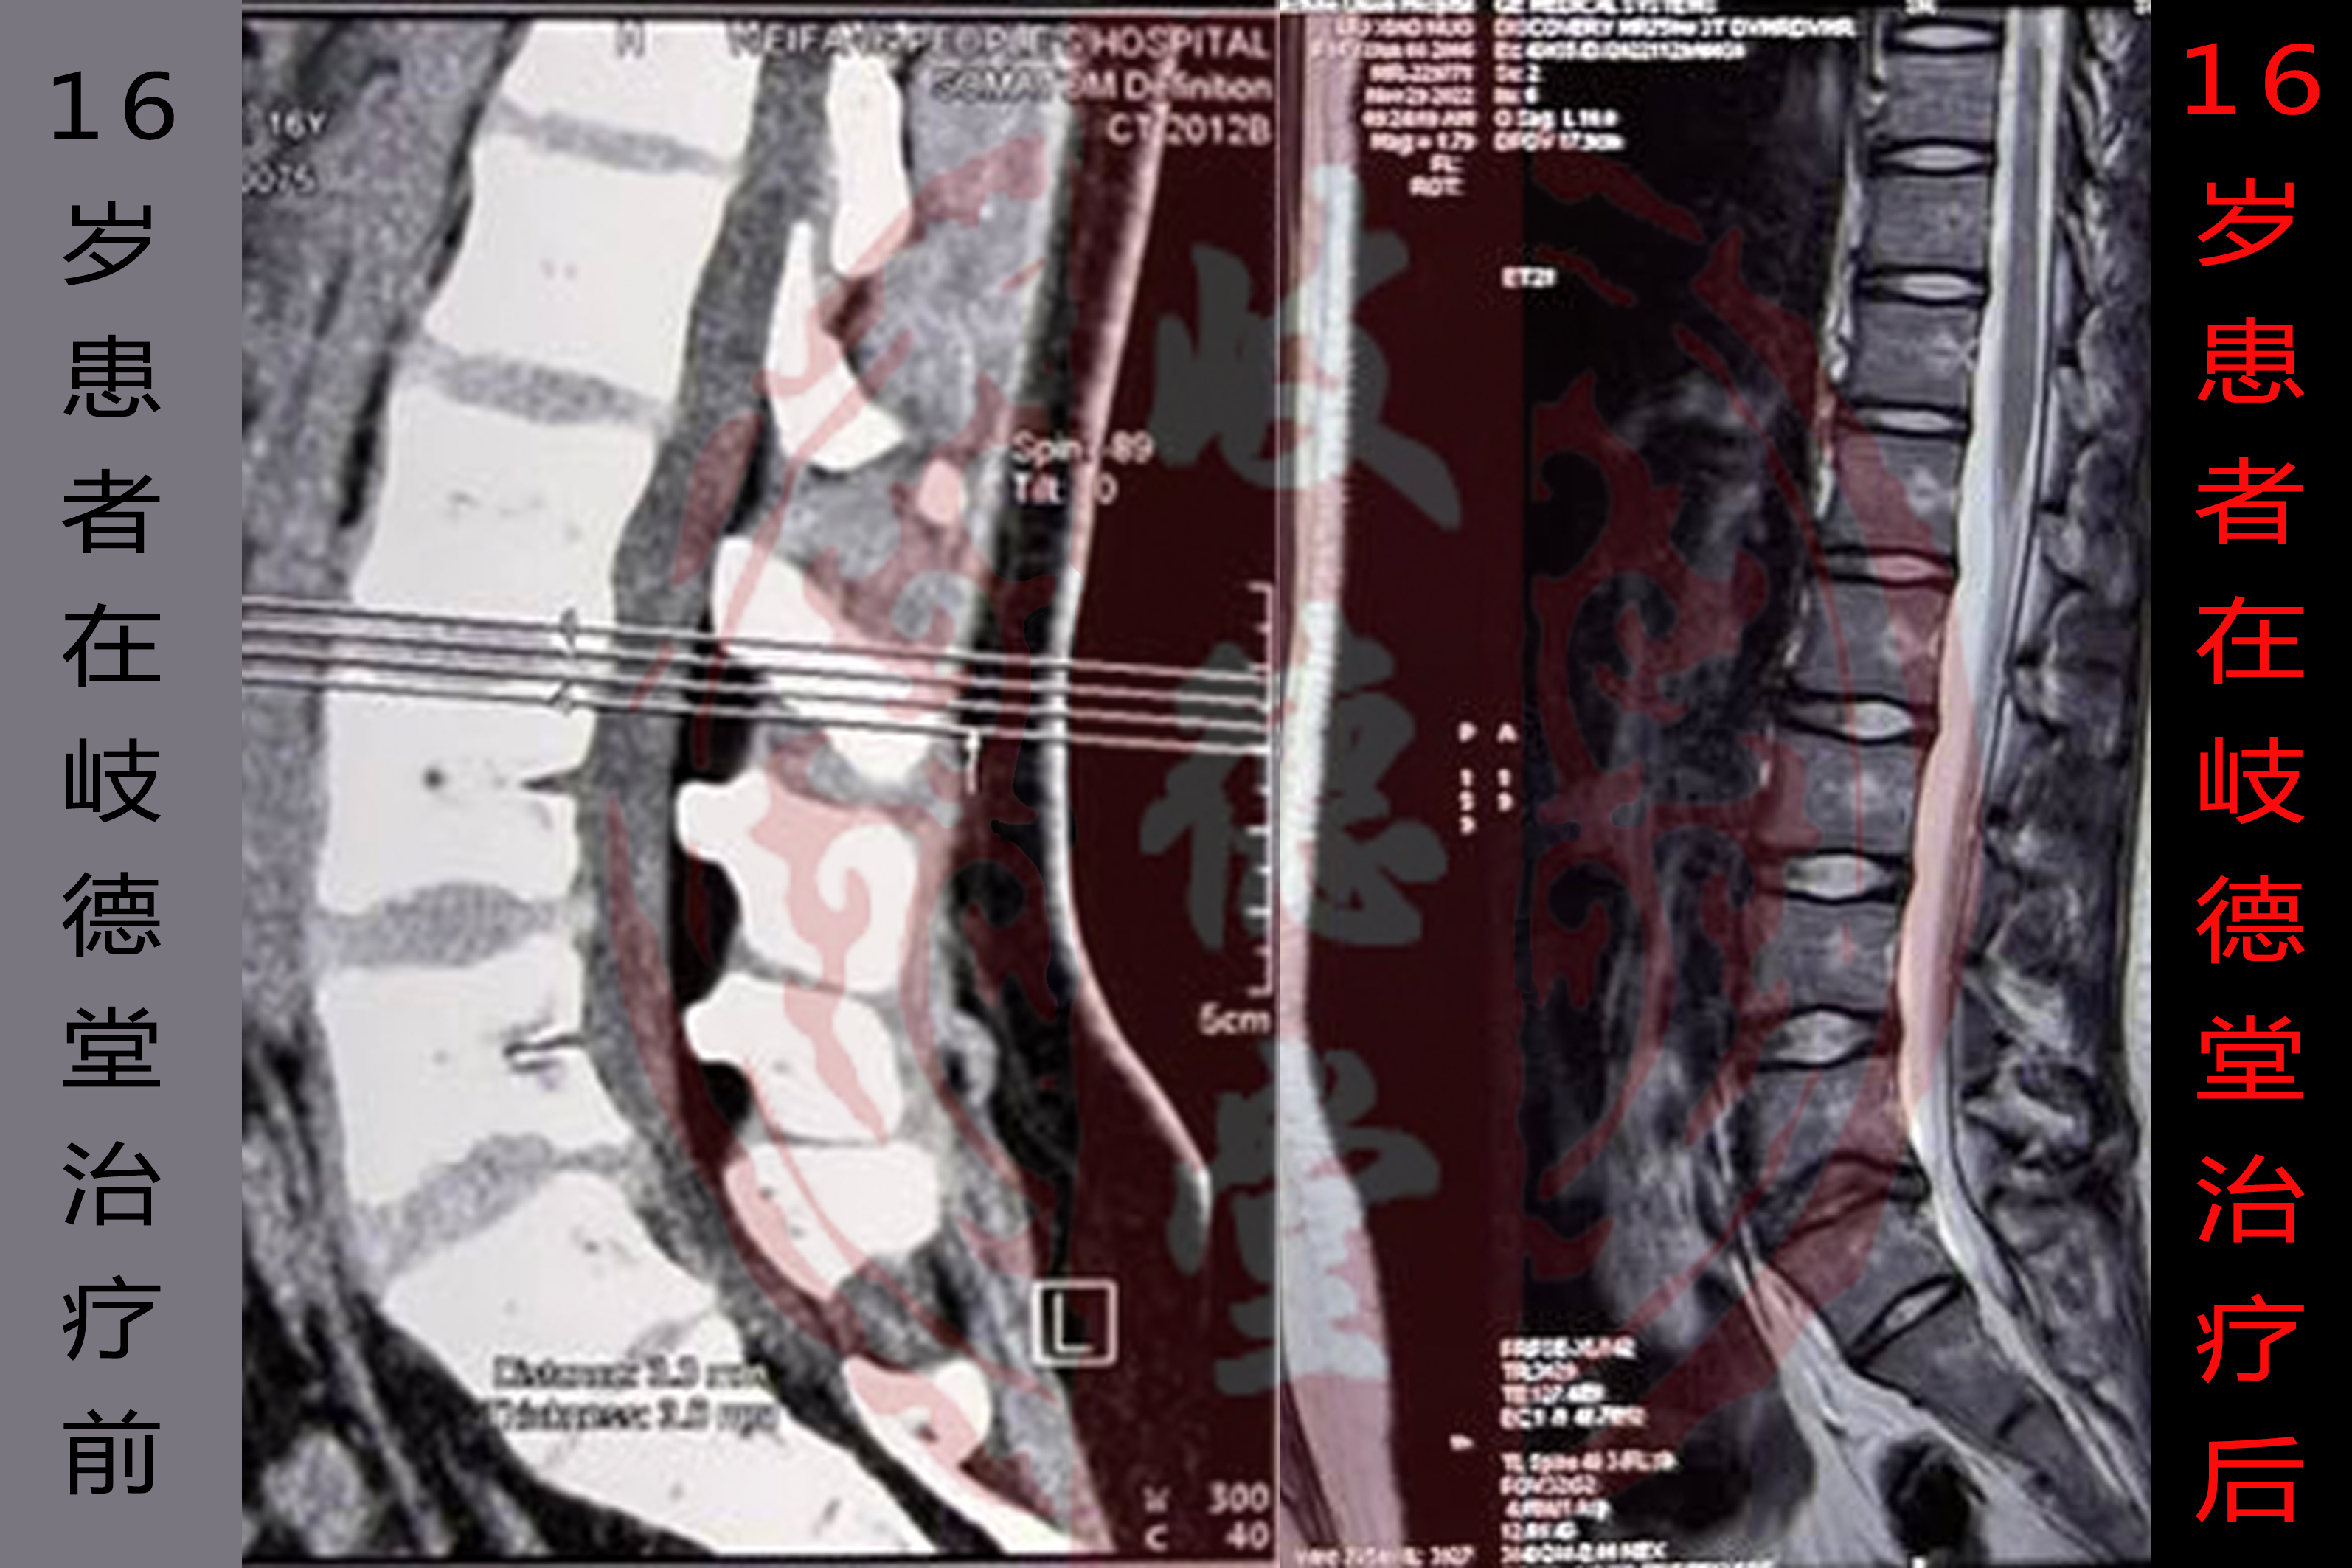

岐德堂中医骨科的李志强院长通过针灸、手法、中药等治疗方法为其治疗2个疗程之后,其腰椎滑脱的问题得到根本性改善,其腰椎影像及诊断报告如下图:

通过上图,可以明显看出岐德堂李志强院长为其进行的2个疗程的治疗后,疗效显著,其腰椎的健康程度大大提升,已经摆脱手术阴影。